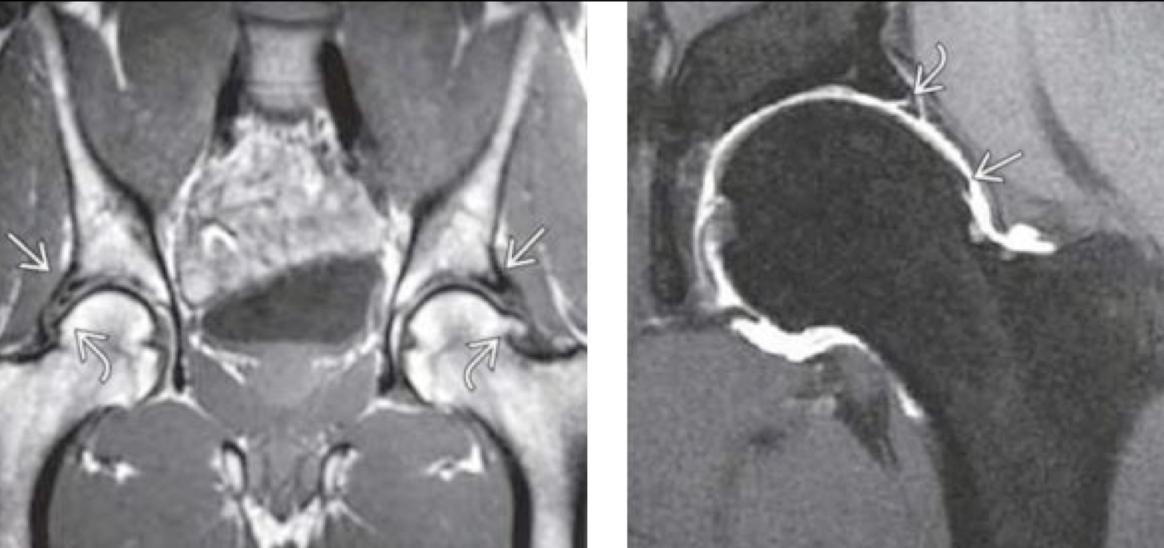

RM PZFAC

A

LOMEJOR

Permite ver edema óseo

pinzamiento leve

quistes

lesión de labrum